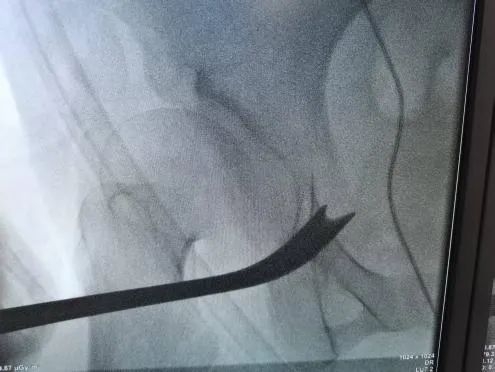

图5-6:术中截骨